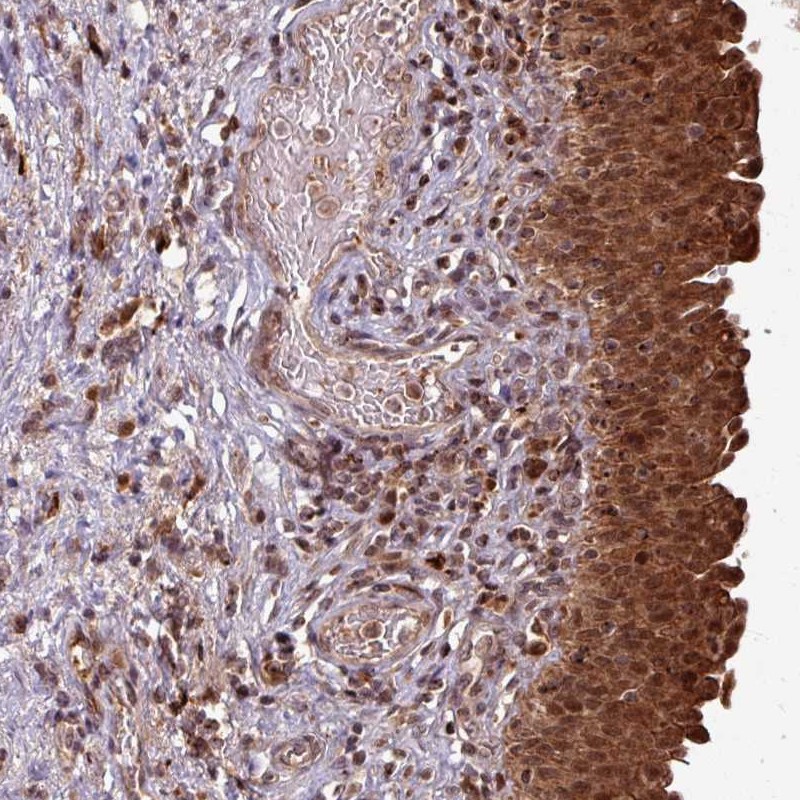

Immunohistochemical staining of human urinary bladder shows strong cytoplasmic and nuclear positivity in urothelial cells.